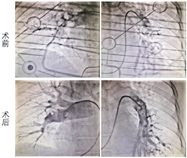

患者诊断"急性肺动脉栓塞"明确,入院密切监测病情时突发心跳呼吸骤停,立即予心肺复苏、气管插管等抢救措施,鉴于其系急性肺栓塞所致心跳呼吸骤停,属于高危患者,有再行灌注治疗的指征。与家属充分沟通后于2022年4月11日急诊行"肺动脉造影+吸栓术+下腔静脉滤器植入术",术中于肺动脉内注入尿激酶20万单位,使用抽吸导管反复抽吸,术顺,术后转入CCU病房继续治疗。

通过持续胸外心脏按压及呼吸机维持生命征,急诊送DSA室,行肺动脉溶栓+吸栓术及下腔静脉滤器植入,继续予以低分子肝素钠抗凝治疗。稳定后改为利伐沙班,抗凝6个月随访。